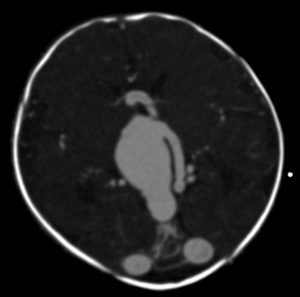

In infants and children, the malformation more commonly presents with neurological symptoms, such as hydrocephalus, macrocephaly, and seizures. VOGM can rarely present in adults, and it typically presents with headache, vomiting, seizures, or subarachnoid hemorrhage [1,11]. Computed tomography (CT) and MRI should be used for comprehensive assessment of the arteriovenous shunt and associated brain changes. CT angiography provides rapid and detailed vascular information, often superior to ultrasound or MRI in depicting both arterial feeders and venous drainage, as demonstrated in the arterial phase images, Figures 4 and 5. MRI is the modality of choice for evaluating the ventricular system and cerebral parenchymal damage, which is important for treatment planning [1].

Figure 5. Axial view of cerebral CT angiography of VOGM during the arterial phase [13].